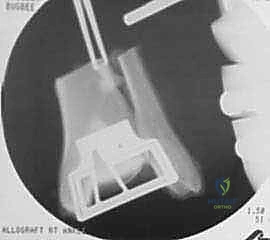

تقنية Osteochondral Allograft Transplantation تعتمد على إزالة الجزء التالف والمريض من عظمة الكاحل (العظم والغضروف معاً) واستبداله بقطعة مطابقة تماماً (طعم) مأخوذة من متبرع (Allograft). هذه القطعة تحتوي على غضروف زجاجي طبيعي حي، وعظم سليم تحته.

الهدف من هذه الجراحة هو "ترميم" المفصل بيولوجياً بدلاً من وضع معدن وبلاستيك، مما يسمح للجسم بدمج العظم المزروع مع عظم المريض، ليعود المفصل للعمل وكأنه طبيعي.

- يتم تشكيل الطعم المأخوذ من المتبرع ليطابق الحفرة التي تم إعدادها في كاحل المريض تماماً (مثل تركيب قطعة البازل).

- يتم إدخال الطعم برفق (Press-fit).

صور إضافية من داخل غرفة العمليات والخطوات الجراحية

ندرك أهمية توثيق الخطوات الجراحية لطلاب الطب والمرضى الراغبين في فهم دقة الإجراء. هذه الصور توضح مراحل زراعة وتثبيت الطعم العظمي الغضروفي بدقة متناهية تحت إشراف أ.د. محمد هطيف.